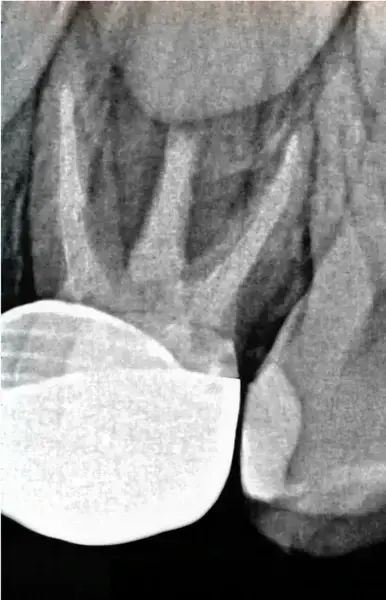

Представеният клиничен случай илюстрира колко лесни могат да бъдат ендодонтските лечения с помощта на Jeni. Пациентът е 6-годишно момче, което посети Dentiland през пролетта заради оплаквания в горната челюст. Интраоралната диагностика потвърди нуждата от лечение на зъб #64 (фиг. 2) и бе поставена диагноза кариес на ранното детство тип II. След обстоен разговор пациентът и родителите му се съгласиха да бъде проведено ендодонтско лечение. Кореновото лечение в такива случаи се състои от петте класически стъпки:

Начало на транса: след анестезия и поставяне на кофердам бяха използвани четири NiTi пили с ендодонтски мотор Jeni с интегриран апекслокатор. Първо бе приложен 25/.12 HyFlex EDM разширител на орифициумите (COLTENE), за да се подготви ендодонтският достъп и да се разшири коронарно. Не е задължително да се създава гладък път. Следващите три пили могат да следват естествения профил на канала по оптимален начин. Реалната обработка на каналите бе направена с пили 20/.05 HyFlex EDM и 25/~ HyFlex EDM OneFile (фиг. 3 и 4). По време на този процес предварително програмираният Jeni режим движи пилите постепенно в апикална посока. Щом се чуе звуков сигнал за иригация, инструментите се извеждат от канала, след което се въвеждат по-дълбоко отпреди. Тази процедура се повтаря, докато не се достигне почти до апекса. В конкретния случай пилите стигнаха до работна дължина още при първото въвеждане. За финал апикалната една трета бе обработена с пила 40/.04, която също бързо бе въведена до пълна работна дължина.